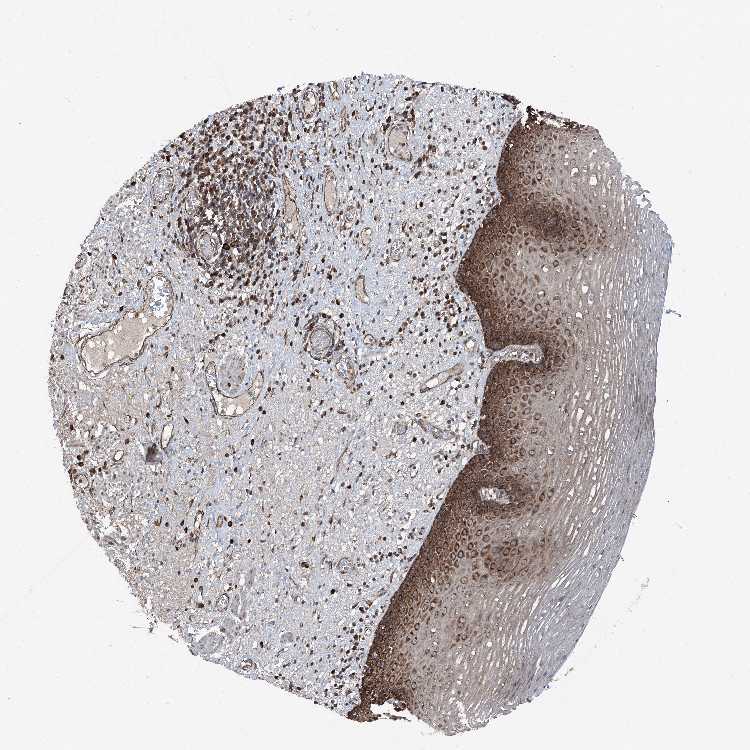

ESOPHAGUS - Antibody stainingi

Antibody staining in the annotated cell types in the current human tissue is reported as not detected, low, medium, or high, based on conventional immunohistochemistry profiling in selected tissues. This score is based on the combination of the staining intensity and fraction of stained cells.

Each image is clickable and will lead to virtual microscopy that enables deeper exploration of all samples and also displays staining intensity scores, fraction scores and subcellular localization as well as patient and tissue information for each sample.

Antibody HPA028516Antibody HPA073571

Squamous epithelial cells HighHigh